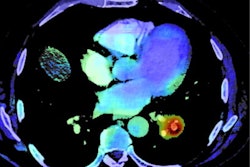

The end-to-end platform will prioritize cases of suspected PE and automatically calculate right ventricle/left ventricle (RV/LV) ratio, bringing together Aidoc's computer-assisted triage offering for PE with Imbio's quantitative imaging software, according to the vendors.